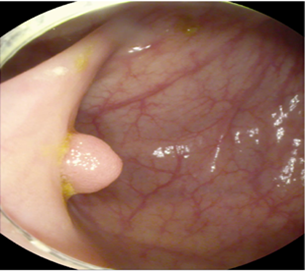

4.1 Dataset Specifications and Augmentation

The study used a publicly available dataset of polyp-frames obtained from the ETIS-Larib database [34], containing 196 polyp images. These images were obtained from 34 different colonoscopy videos of 44 different polyps with various appearances and sizes, having a resolution of 1225×96612259661225\times 966 pixels. The ground truth of polyp areas for polyp datasets is determined by expert video endoscopists. A CNN model trained with such a small amount of data is likely to be meaningless and unstable, so data augmentation was performed on the polyp dataset. Data augmentation had to be performed on the colonoscopy images by considering vivid variations. Otherwise over-fitting would have occurred. In a colonoscopy imagery, polyps exhibits large variations in location, color, and scale. Moreover, variations in brightness and definition also occur due varrying the view-point of the camera. Therefore, in addition to photometric distortions and geometric distortions, we also have considered zooming, shearing, and altering brightness as strategies for data augmentation.

For photometric distortions, we controlled brightness and contrast as an enhancement, while blurring by adding noise with a standard deviation (σ)𝜎(\sigma) of 1.0. Similarly, for geometric distortions, clock-wise rotation of the polyp images with angles of 90°90°, 180°180°, and 270°270° were performed. Zoom-in and zoom-out with zooming parameters such as 30.00% and 10.00% were performed to obtain different scales of polyp images. Lastly, shearing for both the x-axis and the y-axis was performed to shear the images from left to right and top to bottom, respectively. Fig. 4 shows photometric and geometric forms of image augmentation. In this way, we augmented the data set of the ETIS-Larib database from 196 polyp images to 2,156 images, which is more suitable for training the proposed deep CNN model.